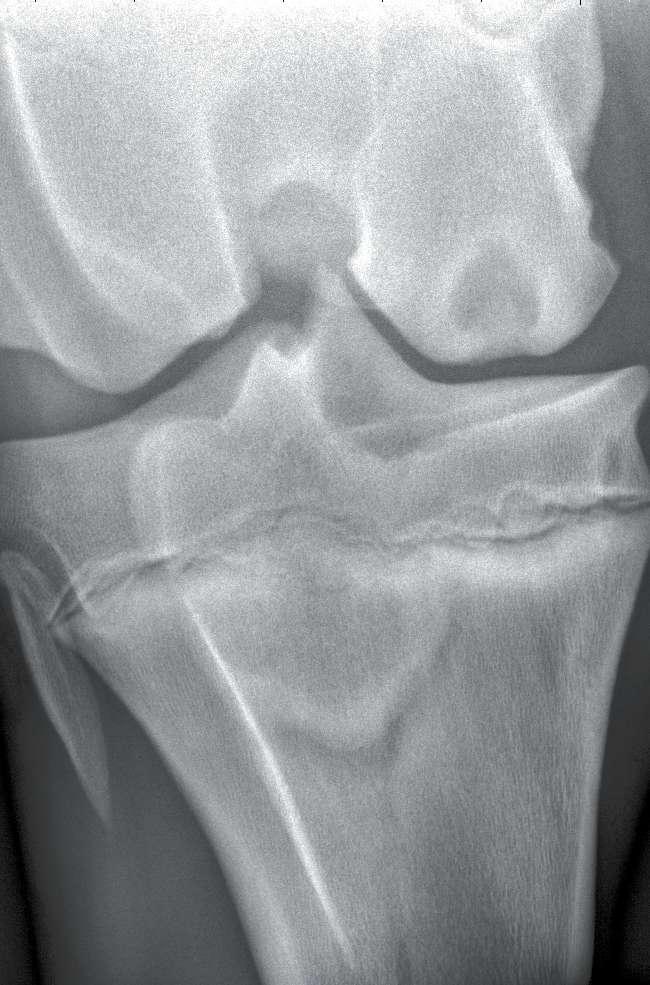

“Radiographic appearances vary. In some cases a radiograph will show a big hole in the bone—maybe ¾-inch in diameter. These typically occur in the medial femoral condyle of the stifle. These lesions can vary from just a flattening of the condyle to a crescent-shaped divot, to a divot that’s 5 mm deep, to a full-blown cyst,” Frisbie says.

“We see these bone cysts/flat areas sometimes on pre-purchase films, and they are not very often associated with lameness. We’ve done some work in which we looked at repository films, and many of these horses were not lame. One study looked at cutting horses and we found a fairly high incidence of cysts,” he says.

“We looked at long-term performance outcomes in 3- and 4-year-old horses, and didn’t see a very high association with flattening on the condyle based on the repository findings,” says Frisbie. When people see these changes on the condyle on prepurchase radiographs, however, they may not understand that not all abnormalities

on the condyle will become a problem.